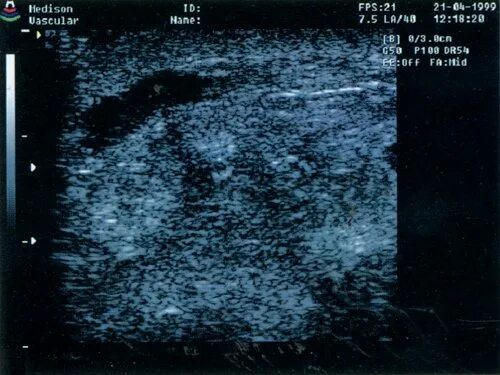

Отечная форма рака молочной